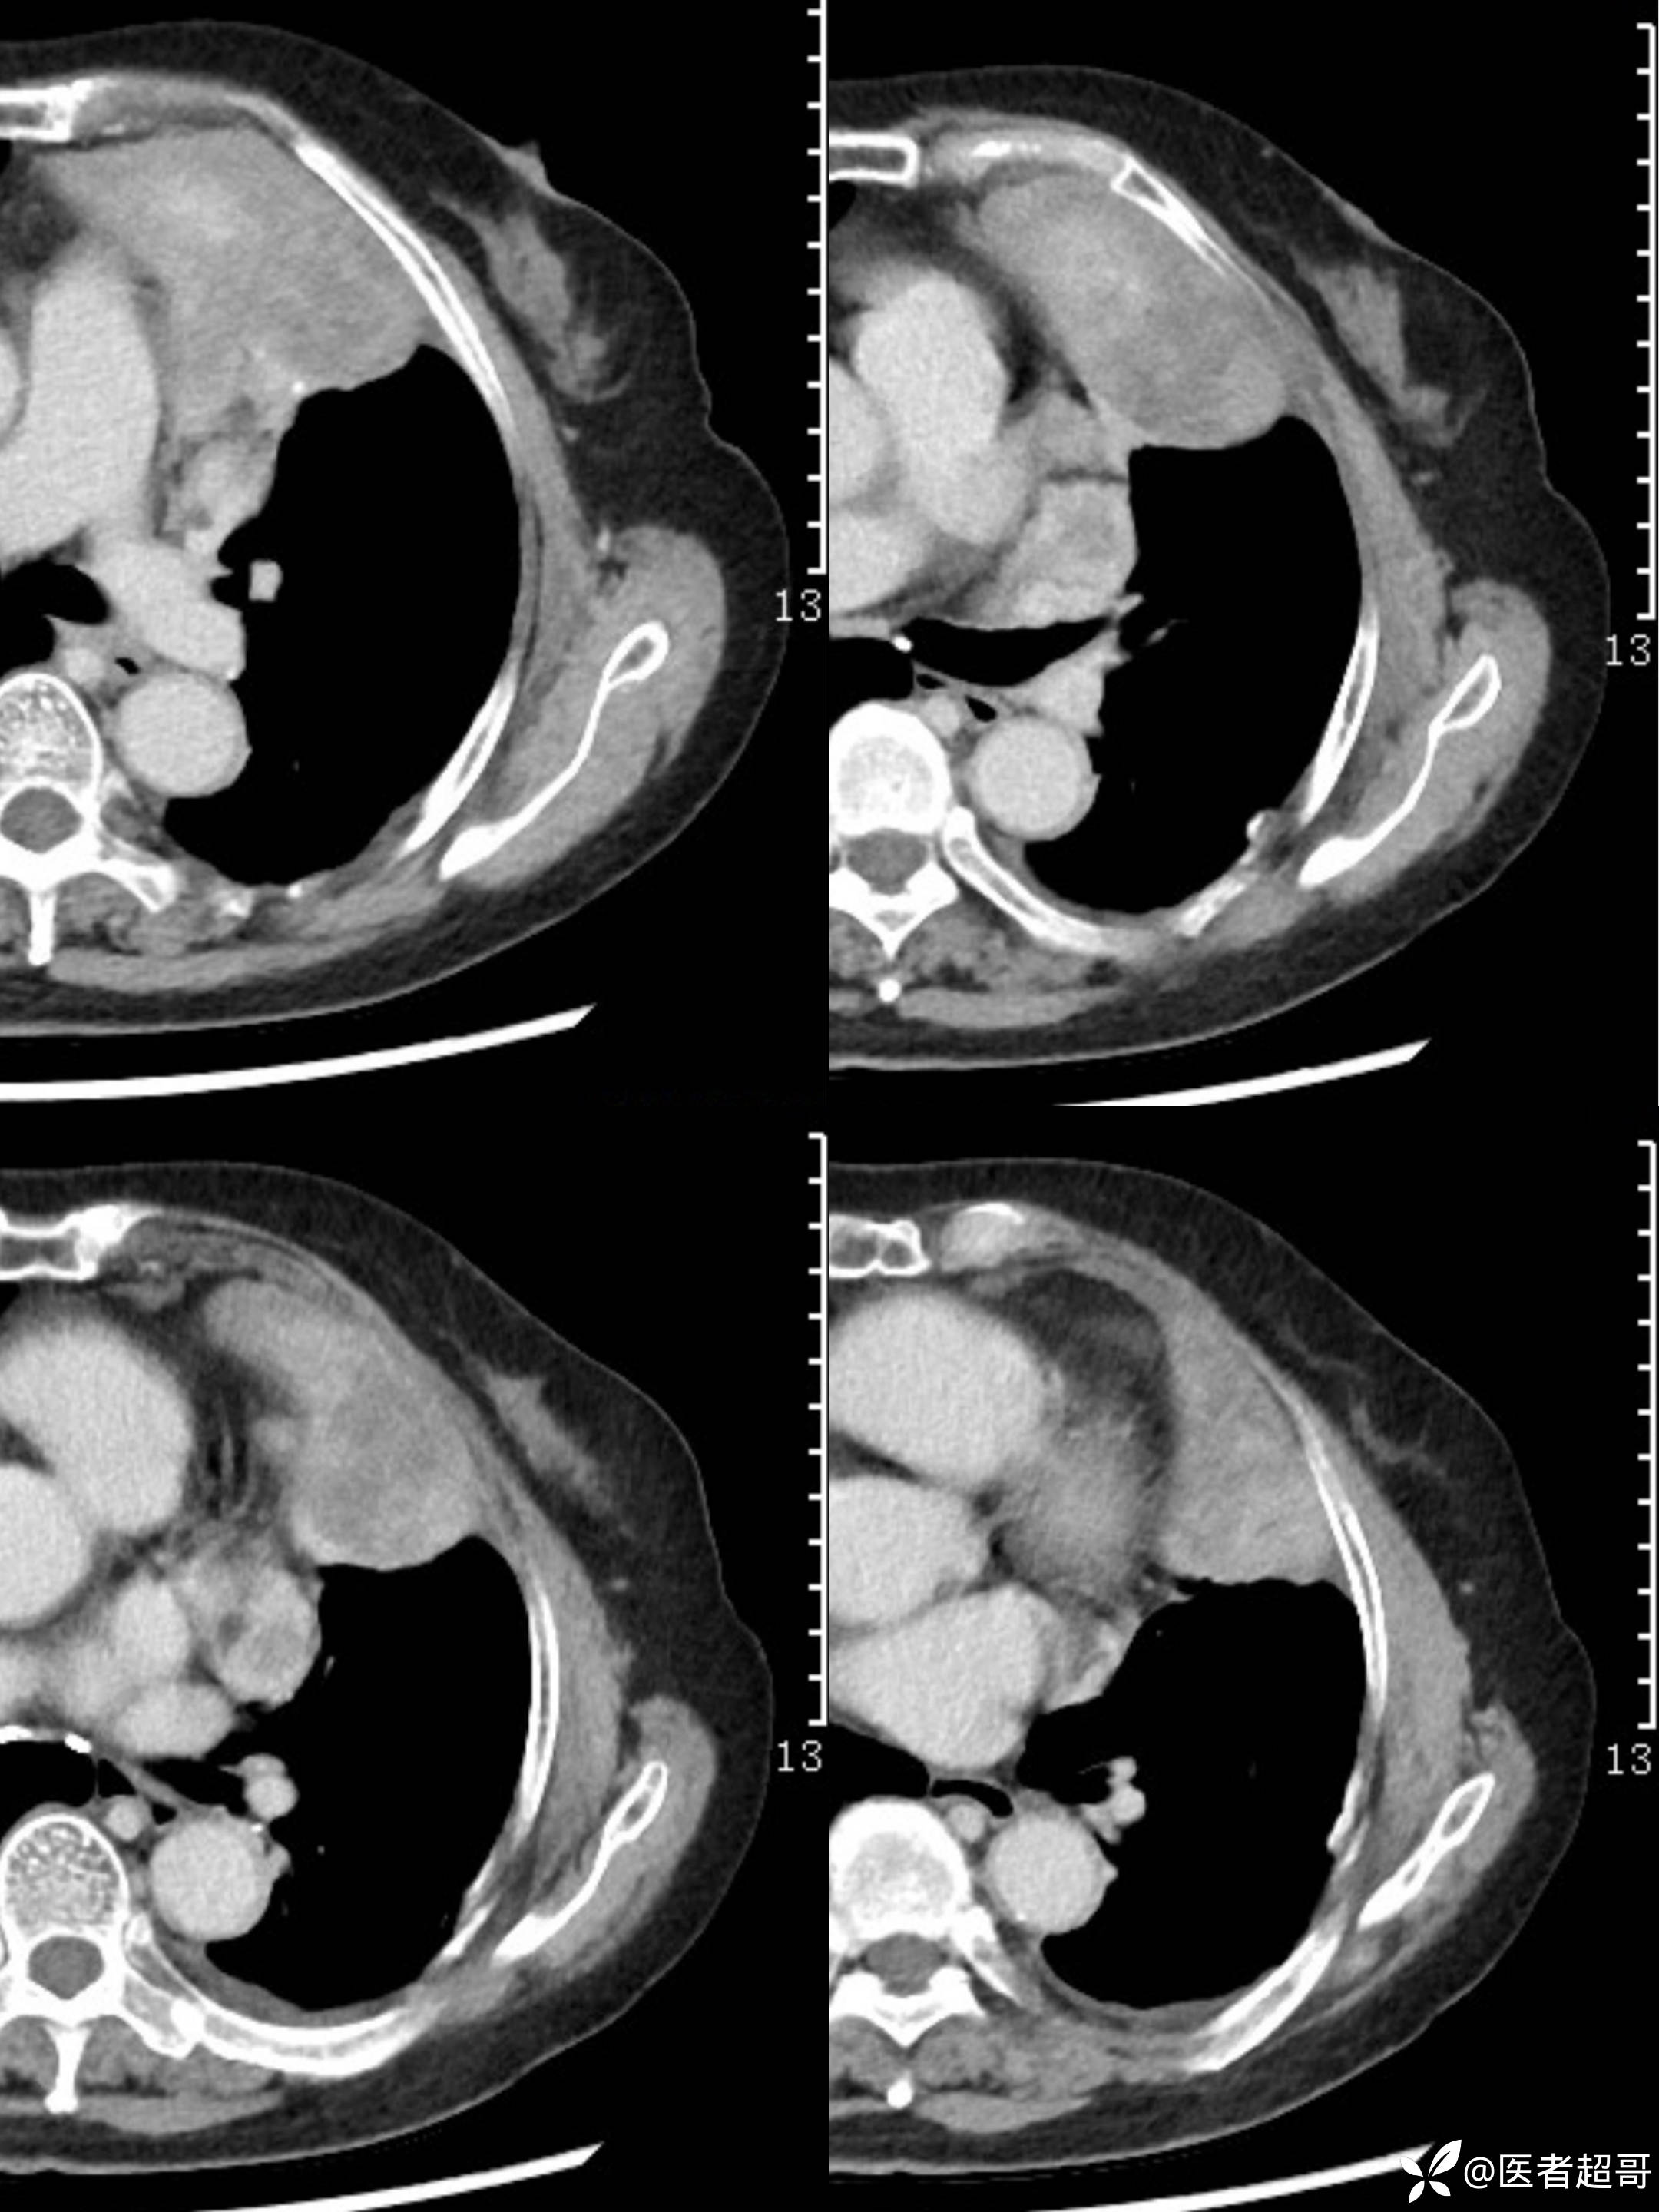

女73岁,体检发现左上纵隔占位1周

患者于1周前体检行CT检查提示:“左上纵隔见不规则团块状软组织密度影,大小约90*63mm”,患者平素偶有头晕,无明显胸闷气急,今为进一步治疗来我院就诊, 门诊以"左上纵隔肿物"收入院。

糖类抗原125(CA125):44.9(正常0-30.2),余实验室检查无殊